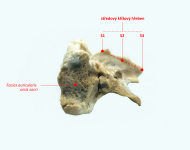

Křížová kost

Křížová kost

Křížová kost se sousedními obratli

Křížová kost se sousedními obratli

Srovnání zdravé křížové kosti a nejnižšího typu vady

Srovnání zdravé křížové kosti a nejnižšího typu vady